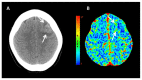

Intracerebral hemorrhage (ICH) accounts for 10% to 20% of all strokes worldwide and is associated with high morbidity and mortality. Neuroimaging is clinically important for the rapid diagnosis of ICH and underlying etiologies, but also for identification of ICH expansion, often as-sociated with an increased risk for poor outcome. In this context, rapid assessment of early hema-toma expansion risk is both an opportunity for therapeutic intervention and a potential hazard for hematoma evacuation surgery. In this review, we provide an overview of the current literature surrounding the use of multimodal neuroimaging of ICH for etiological diagnosis, prediction of early hematoma expansion, and prognostication of neurological outcome. Specifically, we discuss standard imaging using computed tomography, the value of different vascular imaging modalities to identify underlying causes and present recent advances in magnetic resonance imaging and computed tomography perfusion.